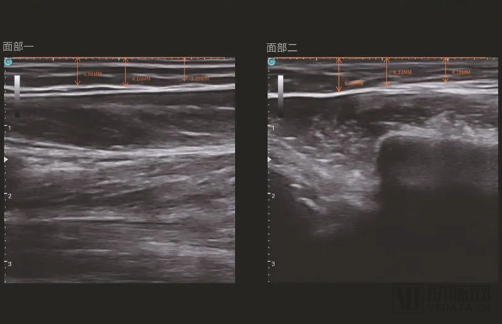

秉持着“让人类更美丽,让人类更健康”的理念,西弥斯医疗研发出了智能超声炮和黄金超声炮,在能量源医美器械中率先实现医疗级诊疗结合技术。在诊断阶段利用超声影像导航,精准定位筋膜层深度,实现“8大区域1分钟急速诊断”智能皮肤定位。治疗阶段则融合了大焦域、超脉冲,AI能量手法自适应调节的智能感应技术,百微米配准技术。无痛无创无恢复期,让求美者们即做即走,安全变美。

智能超声炮设备的超声影像导航  图片由西弥斯医疗提供